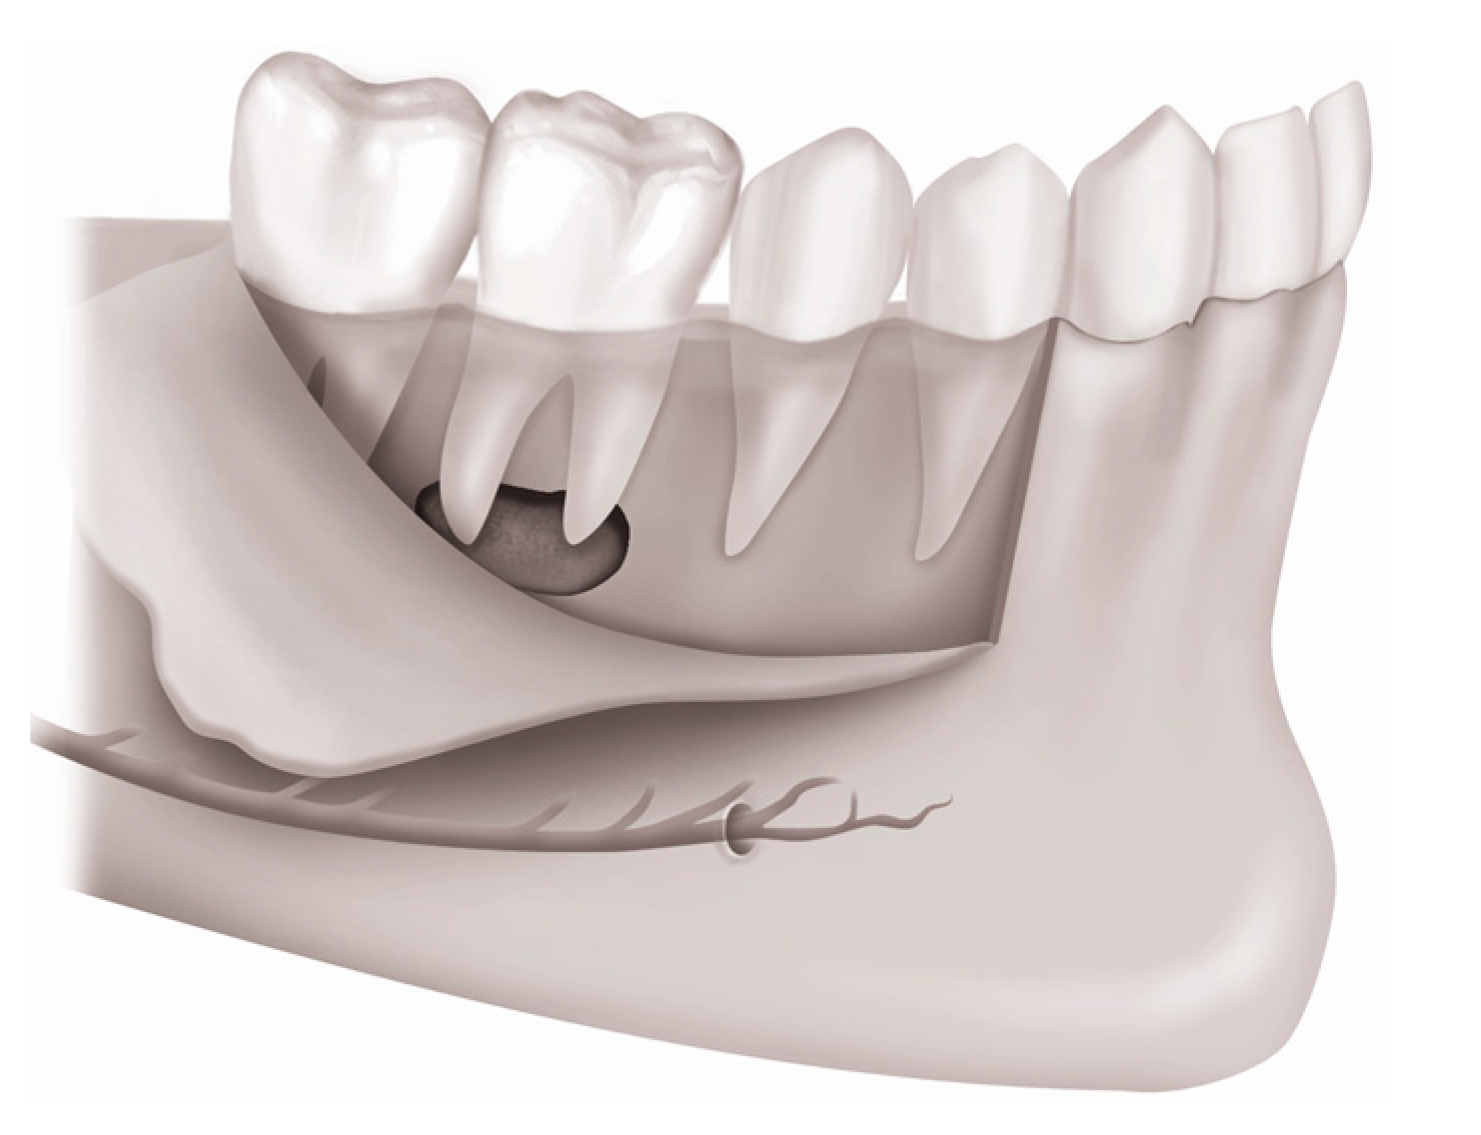

3.2. Osteotomy

- Carcía-Mira, B.; Ortega-Sánchez, B.; Peñarrocha-Diago, M.; Peñarrocha-Diago, M. Ostectomy versus osteotomy with repositioning of the vestibular cortical in periapical surgery of mandibular molars: A preliminary study. Med. Oral Patol. Oral Cir. Bucal. 2010, 15, e628–e632. [Google Scholar] [CrossRef]

- Lee, S.M.; Yu, Y.H.; Wang, Y.; Kim, E.; Kim, S. The application of “bone window” technique in endodontic microsurgery. J. Endod. 2020, 46, 872–880. [Google Scholar] [CrossRef]

- Kim, U.; Kim, S.; Kim, E. The application of “bone window technique” using piezoelectric saws and a CAD/CAM-guided surgical stent in endodontic microsurgery on a mandibular molar case. Restor. Dent. Endod. 2020, 45, e27. [Google Scholar] [CrossRef]